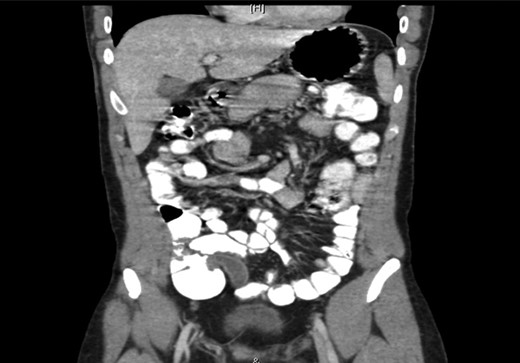

The abdominal X-ray was reported as normal. The abdominal CT scan revealed a dilated appendix measuring 1.6 cm in maximum diameter with no surrounding fat stranding or free fluid. No free air was noted. The wall of the appendix was not interrupted. The liver showed homogeneous enhancement with no focal lesion (Fig. 3). No intrahepatic biliary duct dilatation was observed, and the portal vein and hepatic veins were patent. The spleen, adrenal glands, kidneys and pancreas appeared unremarkable. No free air or free fluid was noted in the abdomen or pelvis. The lung bases and bony skeleton also appeared unremarkable. The findings were consistent with sub-acute appendicitis.

A computed tomography scan of the abdomen showing a dilated appendix with no surrounding fat stranding or free fluid. The wall of the appendix was not interrupted. The liver, spleen, adrenal glands, kidneys, pancreas appeared unremarkable. No free air or free fluid was noted in the abdomen or pelvis. Overall, the findings were consistent with sub-acute appendicitis.